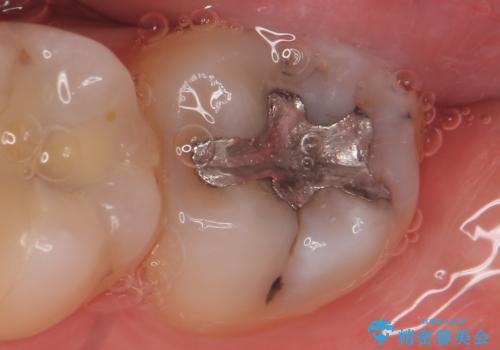

- 古い銀歯を白くしたいといらっしゃった方の症例です。

銀歯及び虫歯を除去後、セラミックインレーにて修復を行いました。